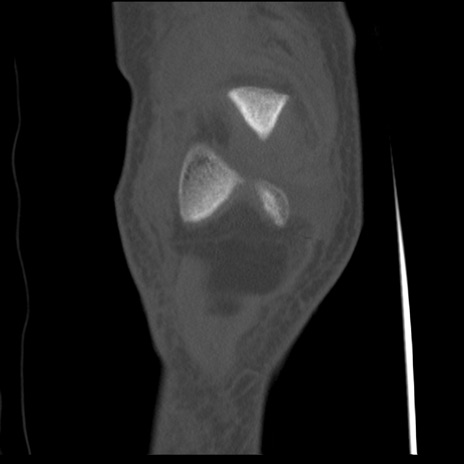

症例28 右膝関節CT(冠状断像)

右膝関節CT

横断像